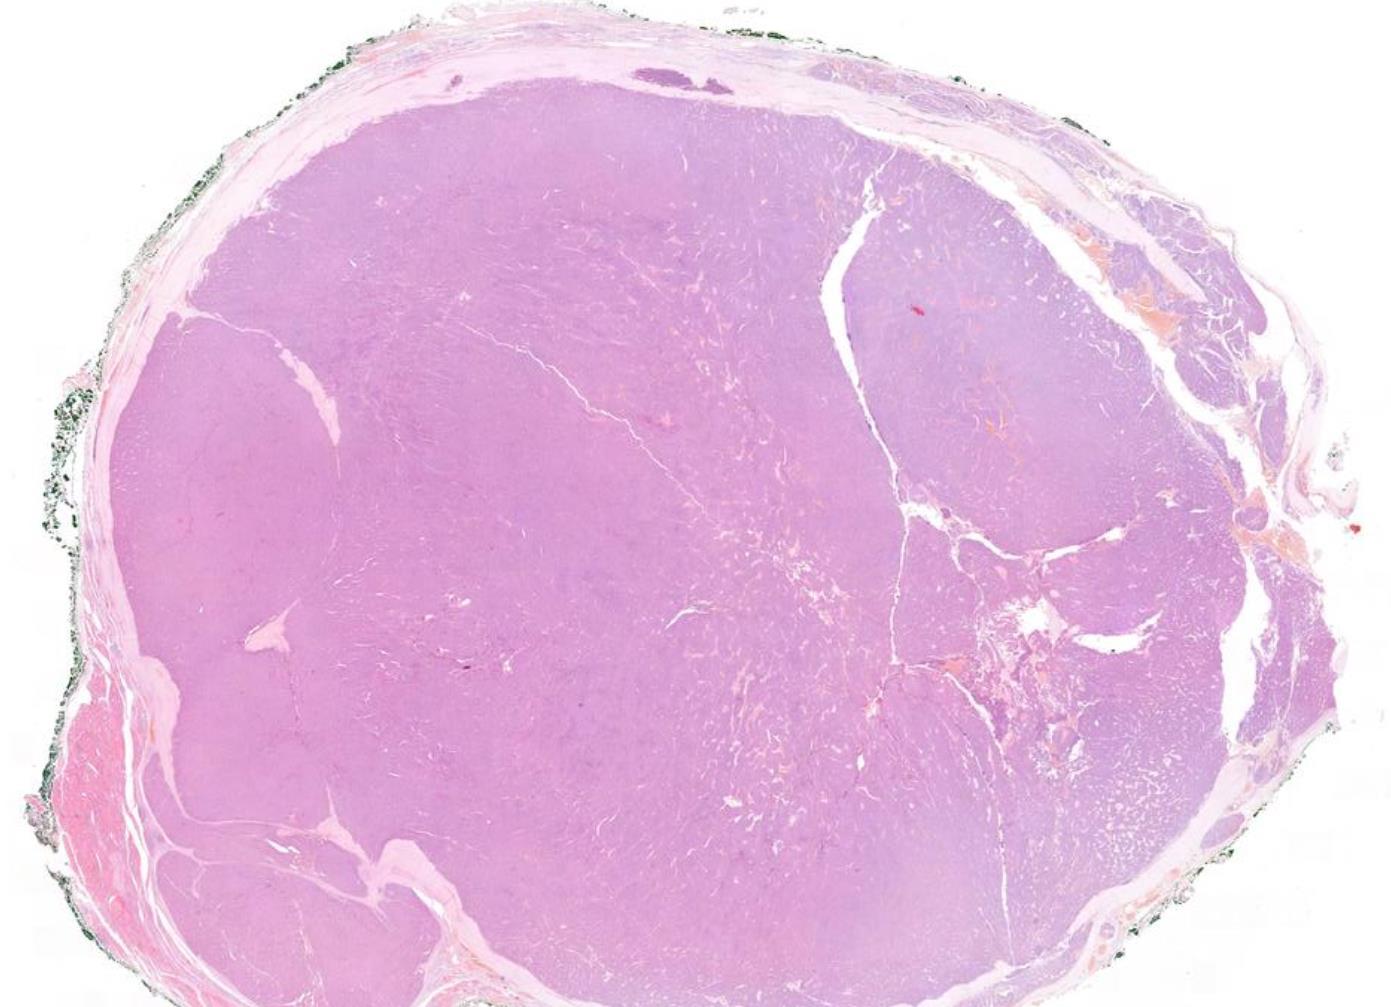

Case

5 52-year-old Female, Left thyroid lobectomy.

Case 5 Diagnosis

Widely invasive follicular thyroid carcinoma

Most FTC are over 20 mm

The capsule is generally thicker in FTC compared to FA/minimally invasive FTC

A diagnosis of widely invasive FTC is based on tumour grossly invading through the thyroid parenchyma often in a multinodular pattern.

Widely invasive FTC can grossly invades extrathyroidal tissue.

Some of the tumour nodules represent large tumour thrombi within vessels.